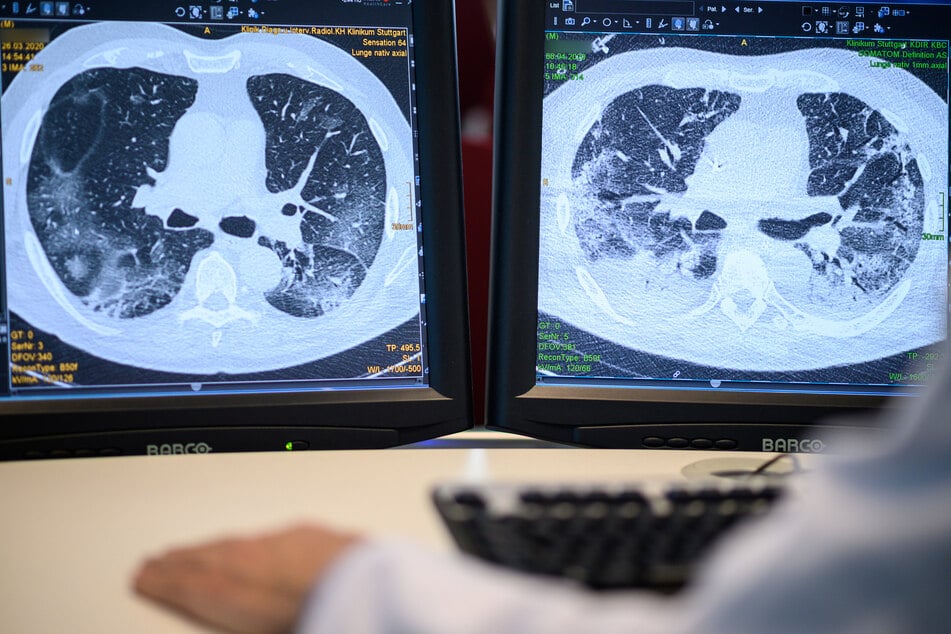

Alles beginnt im September 2024 im LKH Graz II. Die Patientin leidet unter Fieber, Schüttelfrost und körperlicher Schwäche. Die Entzündungswerte sind erhöht, ein CT des Brustkorbs zeigt entzündliche Veränderungen, aber keinen Tumor.